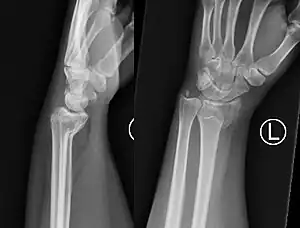

| Colles' fracture | Abraham Colles | distal radius fracture with dorsal angulation, impaction and radial drift | fall on outstretched hand | Colles' fracture at Who Named It? |

|

| Smith's fracture | Robert William Smith | distal radius fracture with volar displacement | fall on outstretched hand with wrist in flexed position | Smith's fracture at Who Named It? |